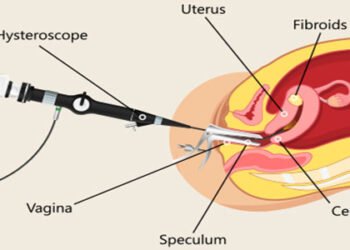

All Laparoscopic Surgeries

Laparoscopy is one of the diagnostic procedures or a surgical treatments which is performed for examining the organs inside the abdomen. It is also termed as diagnostic laparoscopy. In this procedure, an instrument called a laparoscope is used that has a light and camera on it.